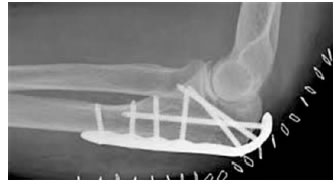

2. Phẫu thuật:

Néo chỉ thép hình số 8, bắt ốc xốp, xuyên đinh kirschner và néo chỉ thép, nẹp vis hoặc cắt bỏ phần mõm khuỷu gãy nát, tái tạo hố sigma lớn.